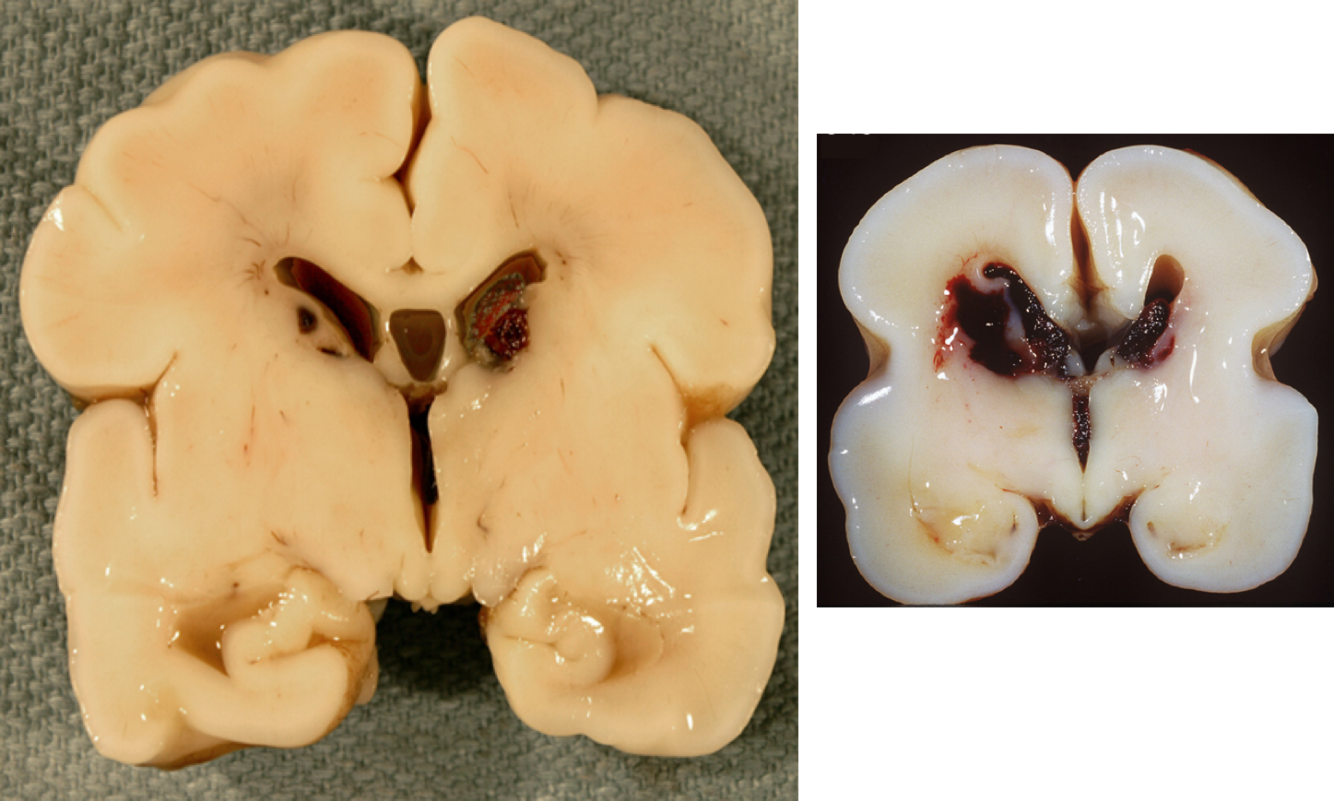

What is this?

intracerebral hemorrhage

What is the leading cause of intracerebral hemorrhage?

hypertension